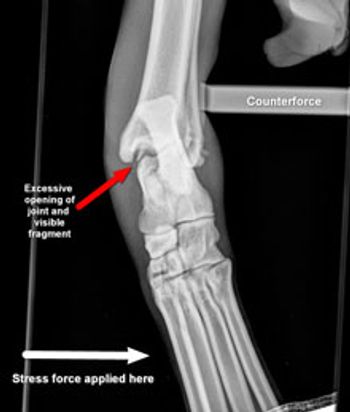

An overview of the diagnosis and treatment of common injuries that cause lameness in dogsIn this article, I will provide an overview of the diagnosis and treatment of these common injuries that cause lameness in dogs:> Soft tissue injuries> Stifle disease (cranial cruciate ligament rupture and patellar luxation)> Hip disease (hip dysplasia)> Elbow disease (elbow dysplasia)> Shoulder disease (soft tissue pathology and ostechondrosis dissecans)> Fractures> Arthritis